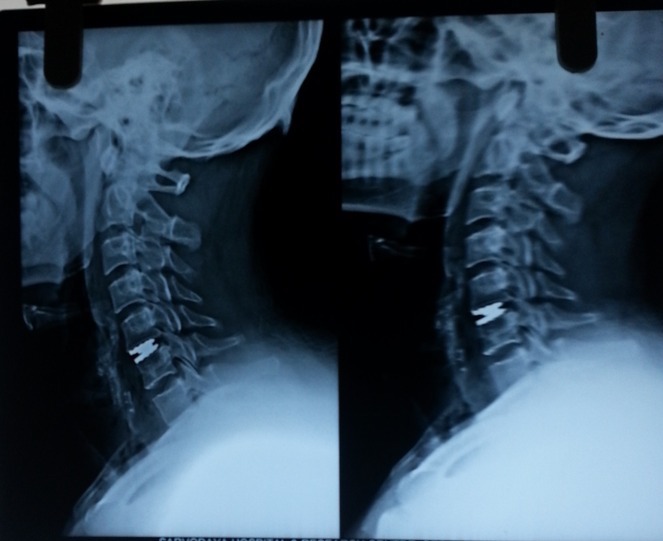

Anterior Cervical Fixation.

cervical